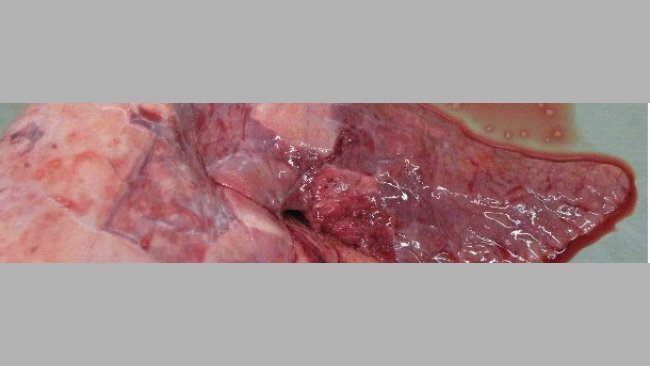

Nos avisan de varios cebaderos integrados en una empresa española en los que han aparecido de forma súbita un porcentaje elevado de cerdos muertos.